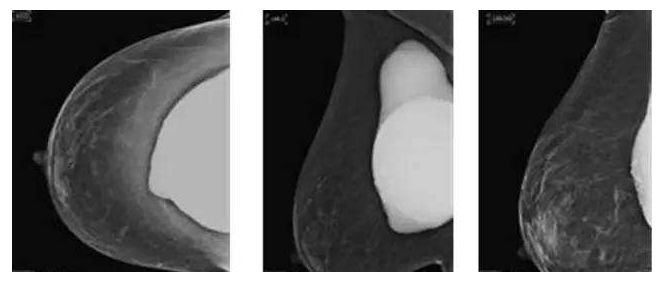

假体老化最常出现的现象,比如囊壁钙化,渗漏,甚至破裂,还会随着人体组织的老化出现下垂问题。

囊壁钙化:硅胶假体在胸部存放时间过长,在硅胶和自身组织包膜之间,就有可能形成钙化沉淀。轻微的钙化不会对人体造成伤害,无需在意。但如果钙化出现较大的结块,而且集中出现在假体周围,便需要做组织取出或手术。

假体渗漏、破裂:囊膜皱褶经反复运动而老化破裂,后期渗漏或破裂,有纤维囊挛缩或急性炎症现象。假体破裂的发生率虽然很低,当假体出现明显的手感变化,形态的变化,那么这个时候就可能出现了假体的破裂,如果出现假体破裂就需要置换假体。

假体松弛下垂

如果出现假体隆胸变软下垂的问题可能是假体置入层次的问题,假体如果是放在胸部腺体下,它会随着自体的胸部往下垂而一起下垂,如果假体放在胸大肌下,那么就会出现腺体往下走,而假体不往下走,就有可能形成四个胸部的情况。